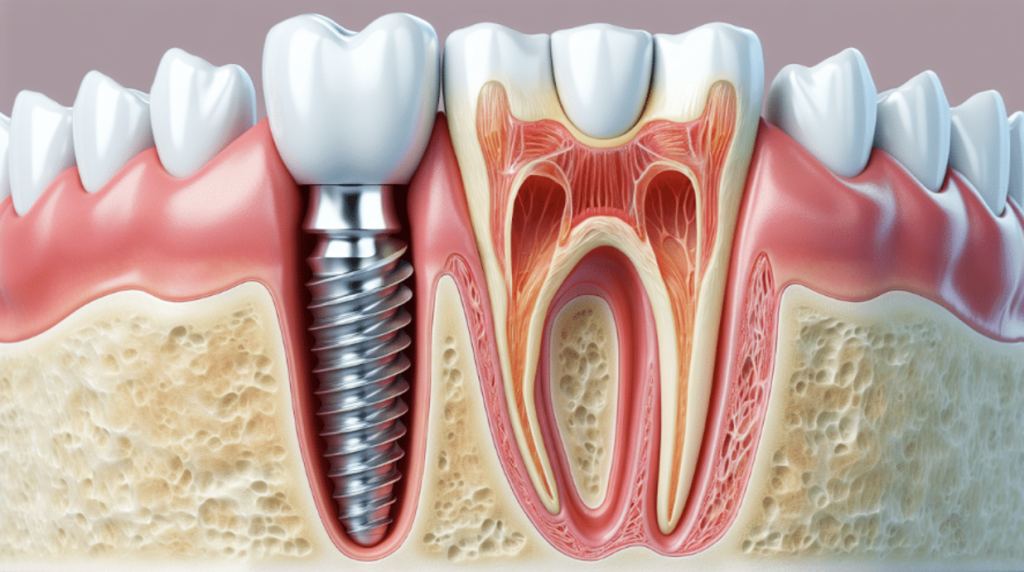

What is a dental implant?

A dental Implant is a titanium “root” that integrates directly with the surrounding bone and replaces the function of the natural tooth. Neoss Implants are made using the best quality medical grade titanium, which is well known for its proven biocompatibility, and have a treated surface to facilitate bone integration.